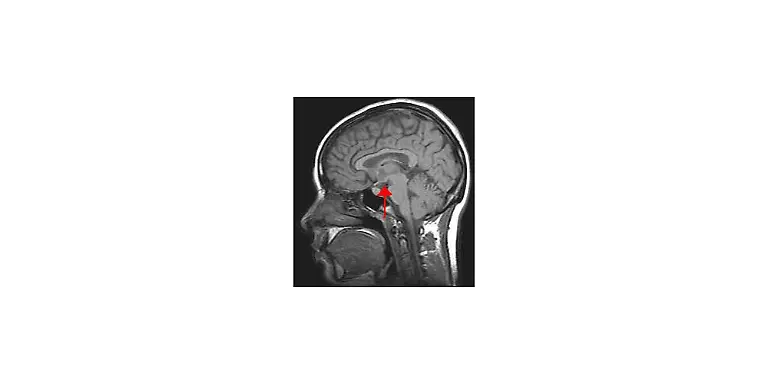

Egal, ob es ums Sehen oder Hören geht, ums Atmen, Sprechen, Rechnen oder Laufen: Stets sind es Milliarden grauer Zellen, die diese Fähigkeiten ermöglichen. Viele verschiedene Bereiche des Gehirns arbeiten zusammen, um die unterschiedlichsten Aufgaben zu lösen. Was wird von wo gesteuert? n-tv.de erklärt, was es mit Frontallappen, Mandelkern & Co. auf sich hat.